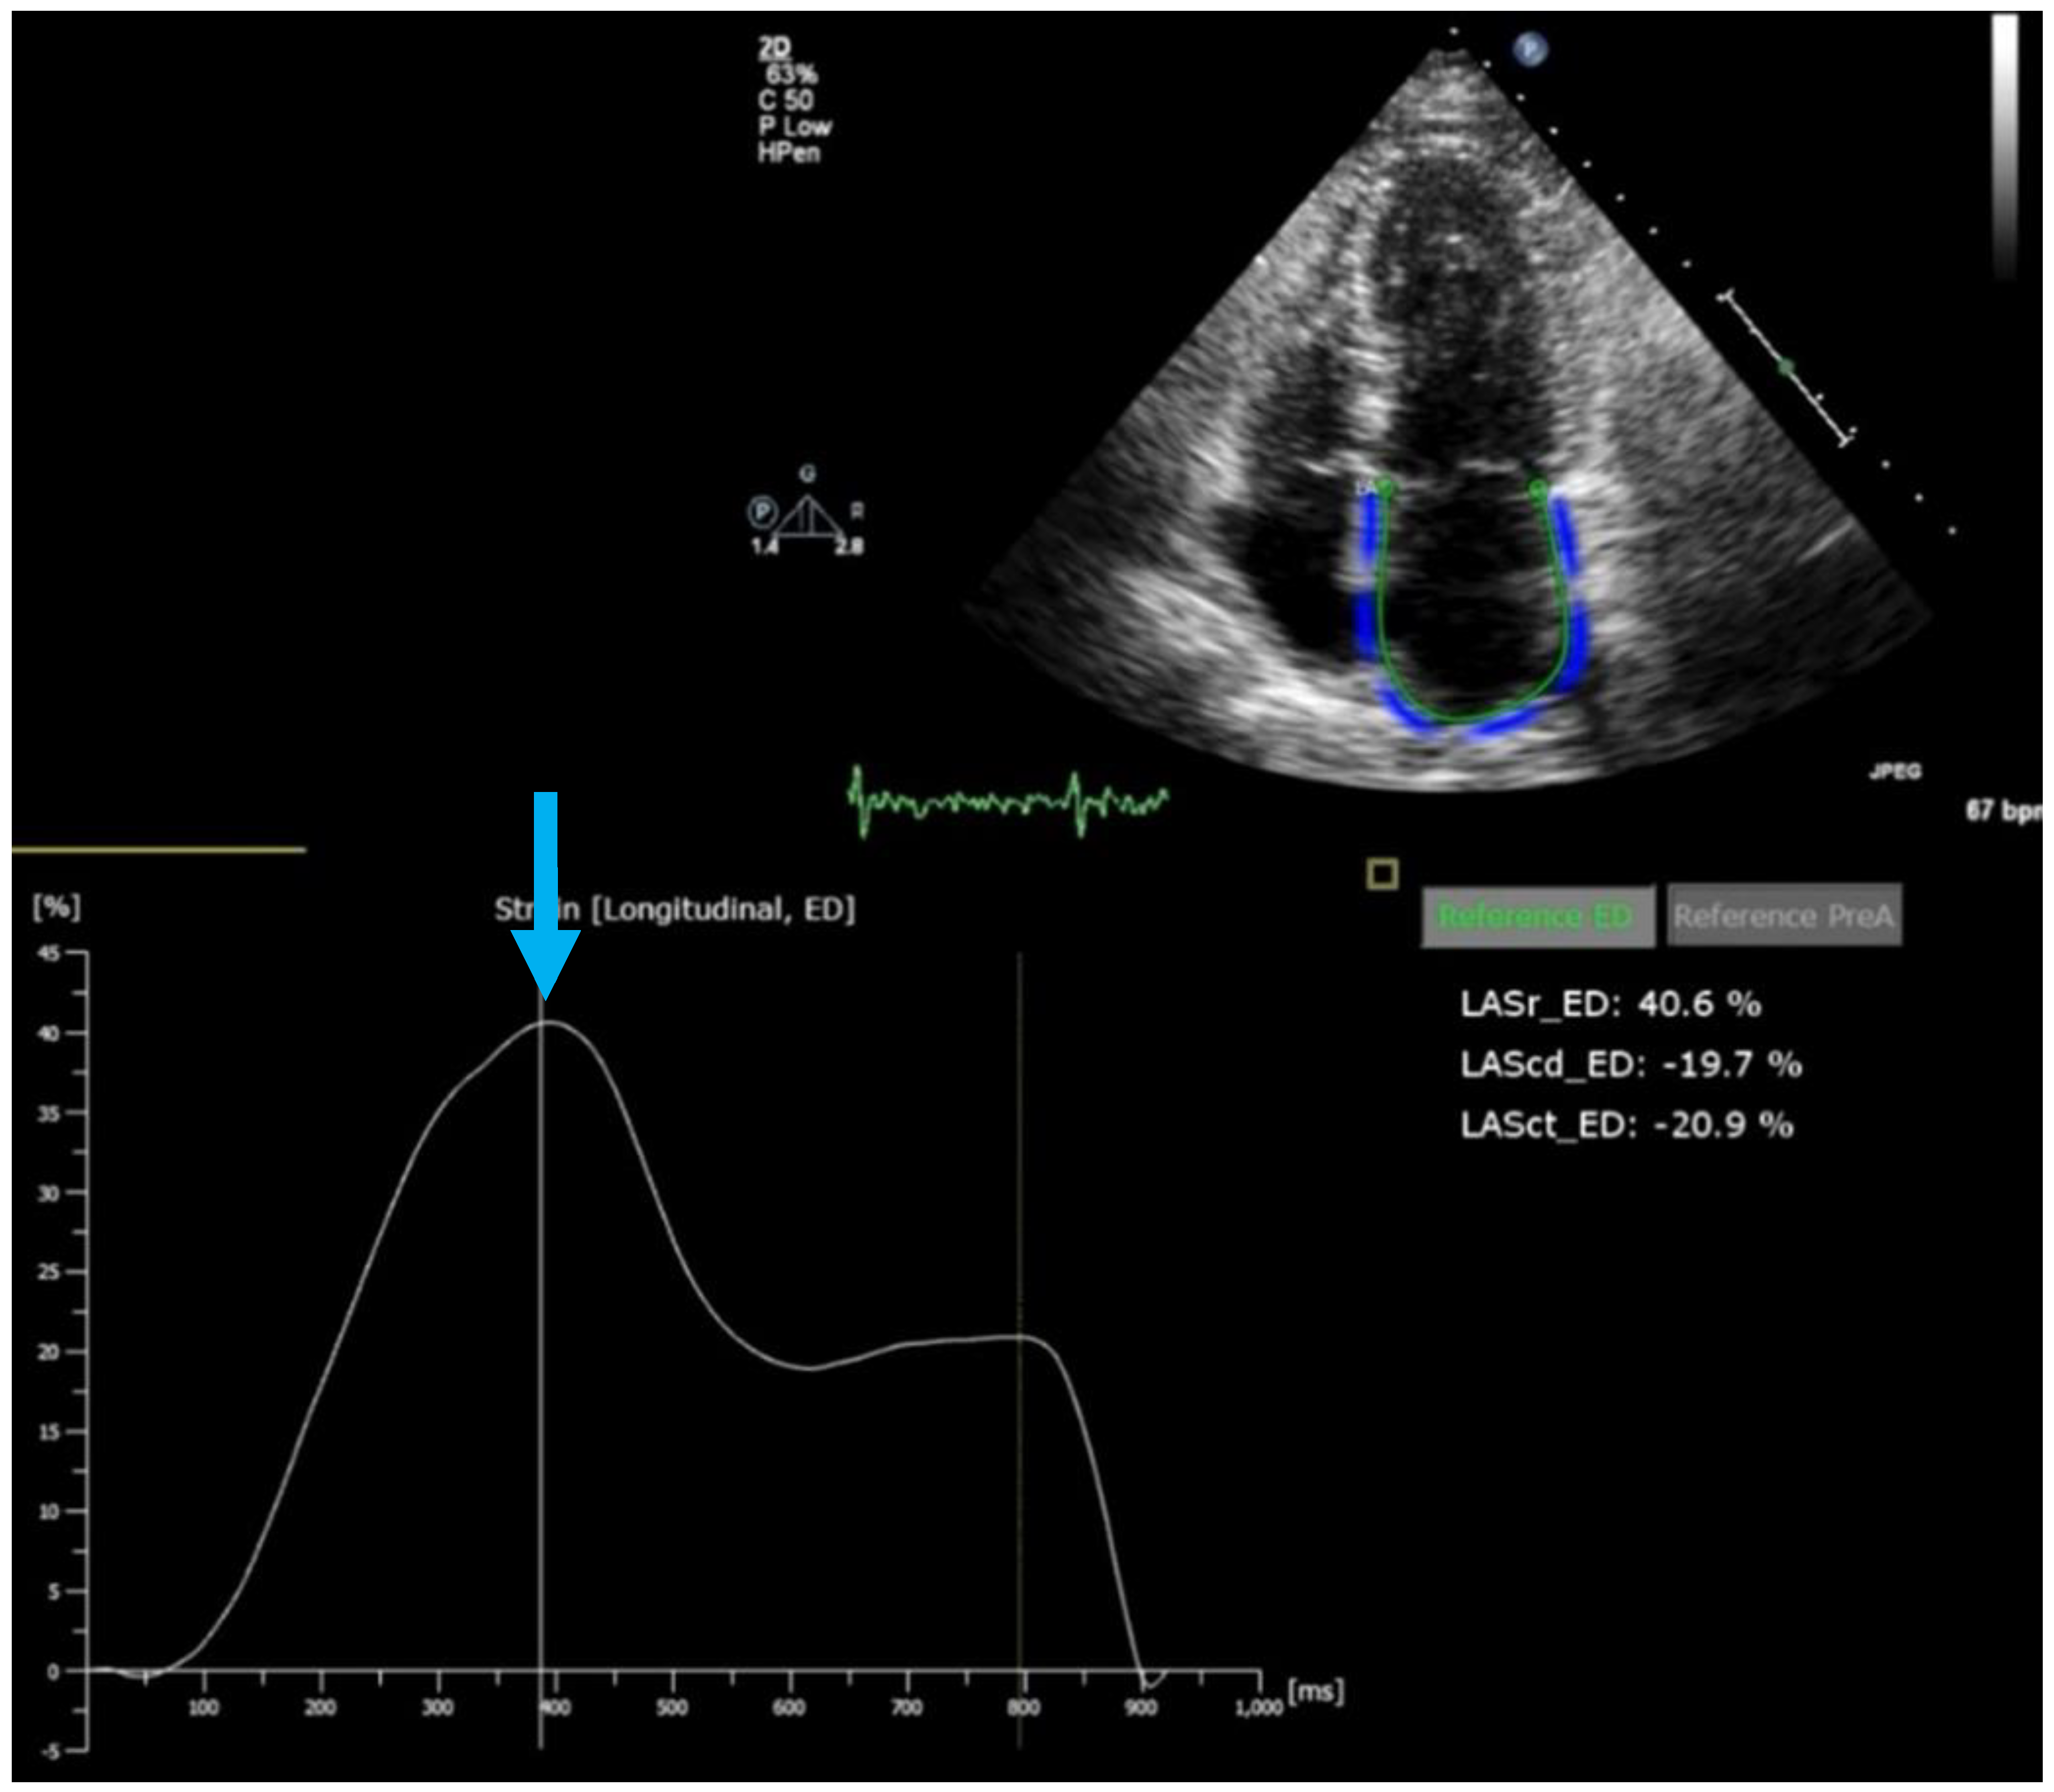

- Inoue, K.; Khan, F.H.; Remme, E.W.; Ohte, N.; Garcıa-Izquierdo, E.; Chetrit, M.; Moñivas-Palomero, V.; Mingo-Santos, S.; Andersen, Ø.S.; Gude, E.; et al. Determinants of left atrial reservoir and pump strain and use of atrial strain for evaluation of left ventricular filling pressure. Eur. Heart J. Cardiovasc. Imaging 2021, 23, 61–70. [Google Scholar] [CrossRef] [PubMed]

- Obokata, M.; Negishi, K.; Kurosawa, K.; Arima, H.; Tateno, R.; Ui, G.; Tange, S.; Arai, M.; Kurabayashi, M. Incremental diagnostic value of la strain with leg lifts in heart failure with preserved ejection fraction. JACC Cardiovasc. Imaging 2013, 6, 749–758. [Google Scholar] [CrossRef]